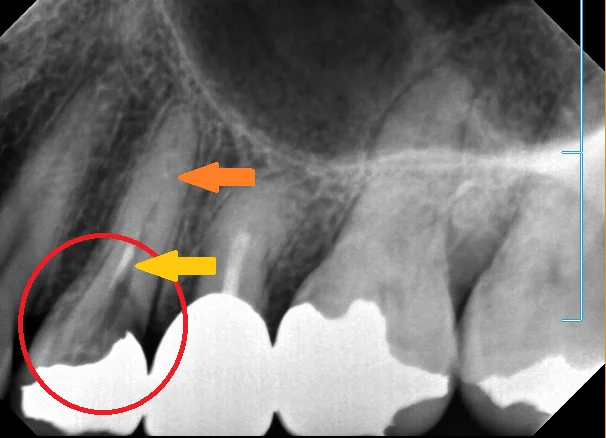

では、これが術前のレントゲンです。

保険のメタルインレーが入っており、その脇から中に大きく虫歯が入り込んでいます。 (画像の赤丸の所)

ただ、この歯、どうやら神経の治療をされていたようなんですが・・・ なんかこう・・・ちょろっとしか薬が入っていません。 (画像の黄色の矢印の所)

幸い根の先に膿が溜まったりはしていませんが、虫歯の期間が長かったせいか根管(神経の入っている管)の中に高度に石灰化が起こってしまっています。 (画像のオレンジの矢印の所)